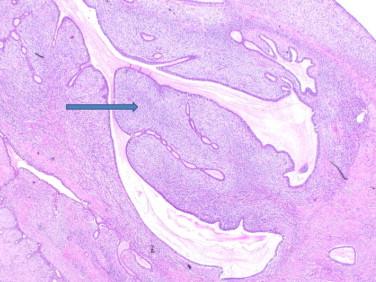

Two females in their fifties were diagnosed with malignant phyllodes tumour associated with heterologous sarcomatous differentiation. The first patient, aged 50 had phyllodes tumour with chondrosarcoma, osteosarcoma and ductal carcinoma-in-situ. The second patient, aged 53 had phyllodes tumour with osteosarcoma and liposarcoma.